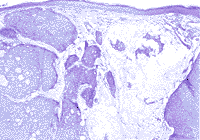

图2 粘蛋白性癌。真皮内有大小不等、不规则形状的小叶,与一片含粘蛋白的肿瘤细胞团相邻(苏木素-伊红染色,原大×40)